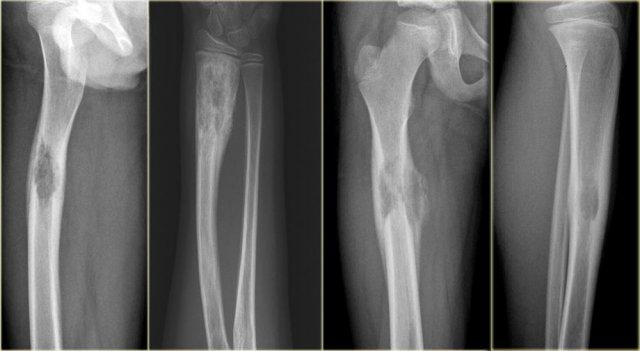

Ở bên trái có hai tổn thương khác được chứng minh là u sụn ác tính (chondrosarcoma).

Lưu ý rằng vôi hóa không phải là dấu hiệu bắt buộc trong u sụn ác tính (chondrosarcoma).

Ở bên trái là tổn thương tiêu xương thùy múi, một phần không rõ ranh giới ở đầu trên xương cánh tay.

Sự hiện diện của các vôi hóa gợi ý đây là một khối u sụn.

Các phần tiêu xương có xâm lấn và phá hủy vỏ xương nên làm tăng nghi ngờ về sarcoma sụn độ cao.